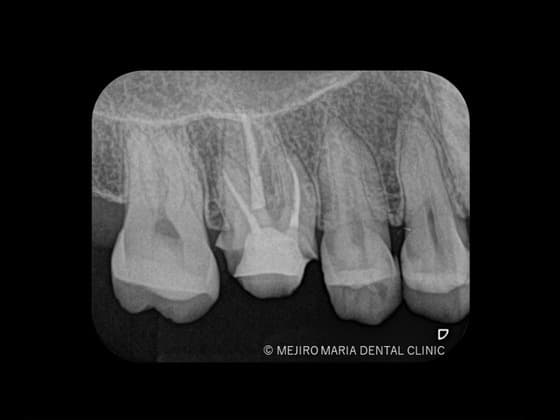

レントゲンの画像

歯髄が不可逆性歯髄炎なのか、可逆性歯髄炎なのかを確実に診断するためには組織切片のサンプルが必要になるため、事実上不可能です。そのため、歯髄の診断では冷たいものや温かいものなどに対する歯髄の反応を見極めることが重要になります。レントゲン、触診、温度診などの診査結果を総合的に踏まえて、現在の歯髄の状況を診断するためには、十分に診査時間を確保することが必要になります。

歯の神経(歯髄)に細菌の感染が広がる